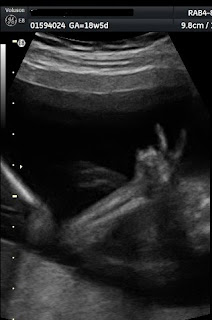

This picture was taken today at 20 weeks, 5 days...that's about 5 months along.